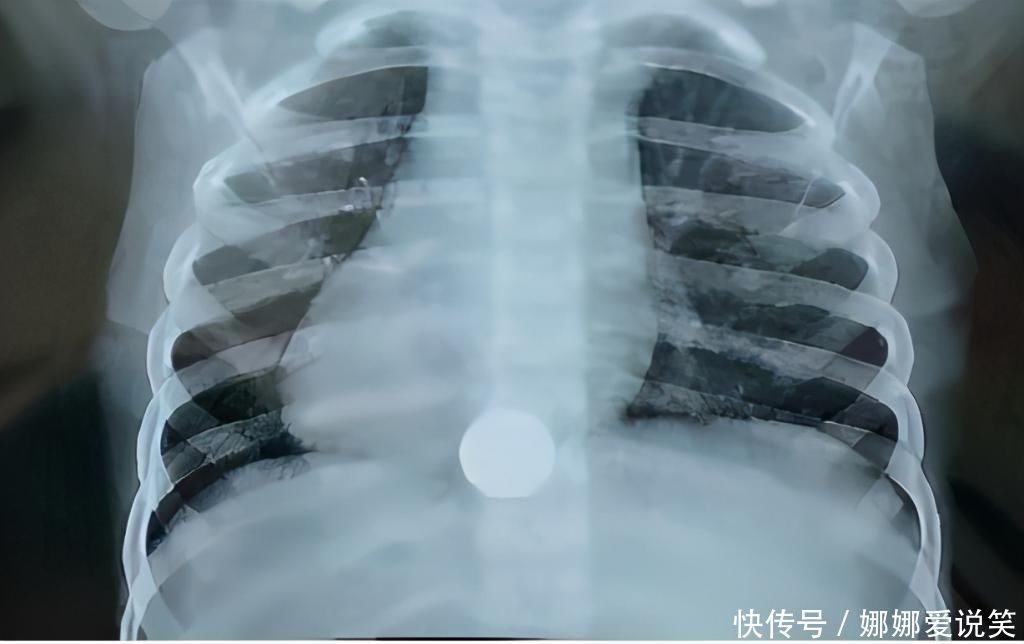

另外一例小孩误吞硬钱币的事,跟前面的情形差不多。这是一个两岁多一点的男孩,同样因为家人照顾欠周,这位充满好奇心的宝宝吞下了一枚硬币。妈妈在上班时接到家人的电话,匆忙赶回家中,一了解又是一枚5角钱的硬币。孩子妈妈很着急,打电话向我告急,问怎么办好?如同前面一样,我初步了解大致的情况后,也是让赶紧去医院,不要侥幸会排出。不过这个孩子去到医院通过胸腹x光联片,发现硬币已经落入了宝宝的胃内。医生将情况与家长沟通了一会,征求家长的意见,最后决定先暂行观察。二天后家长扒拉便便终于从中找到了这枚宝贵的硬币。(已经落入胃肠的异物,体积又较小,也有可能会自行排出。但要密切观察,有异常情况随时要手术)